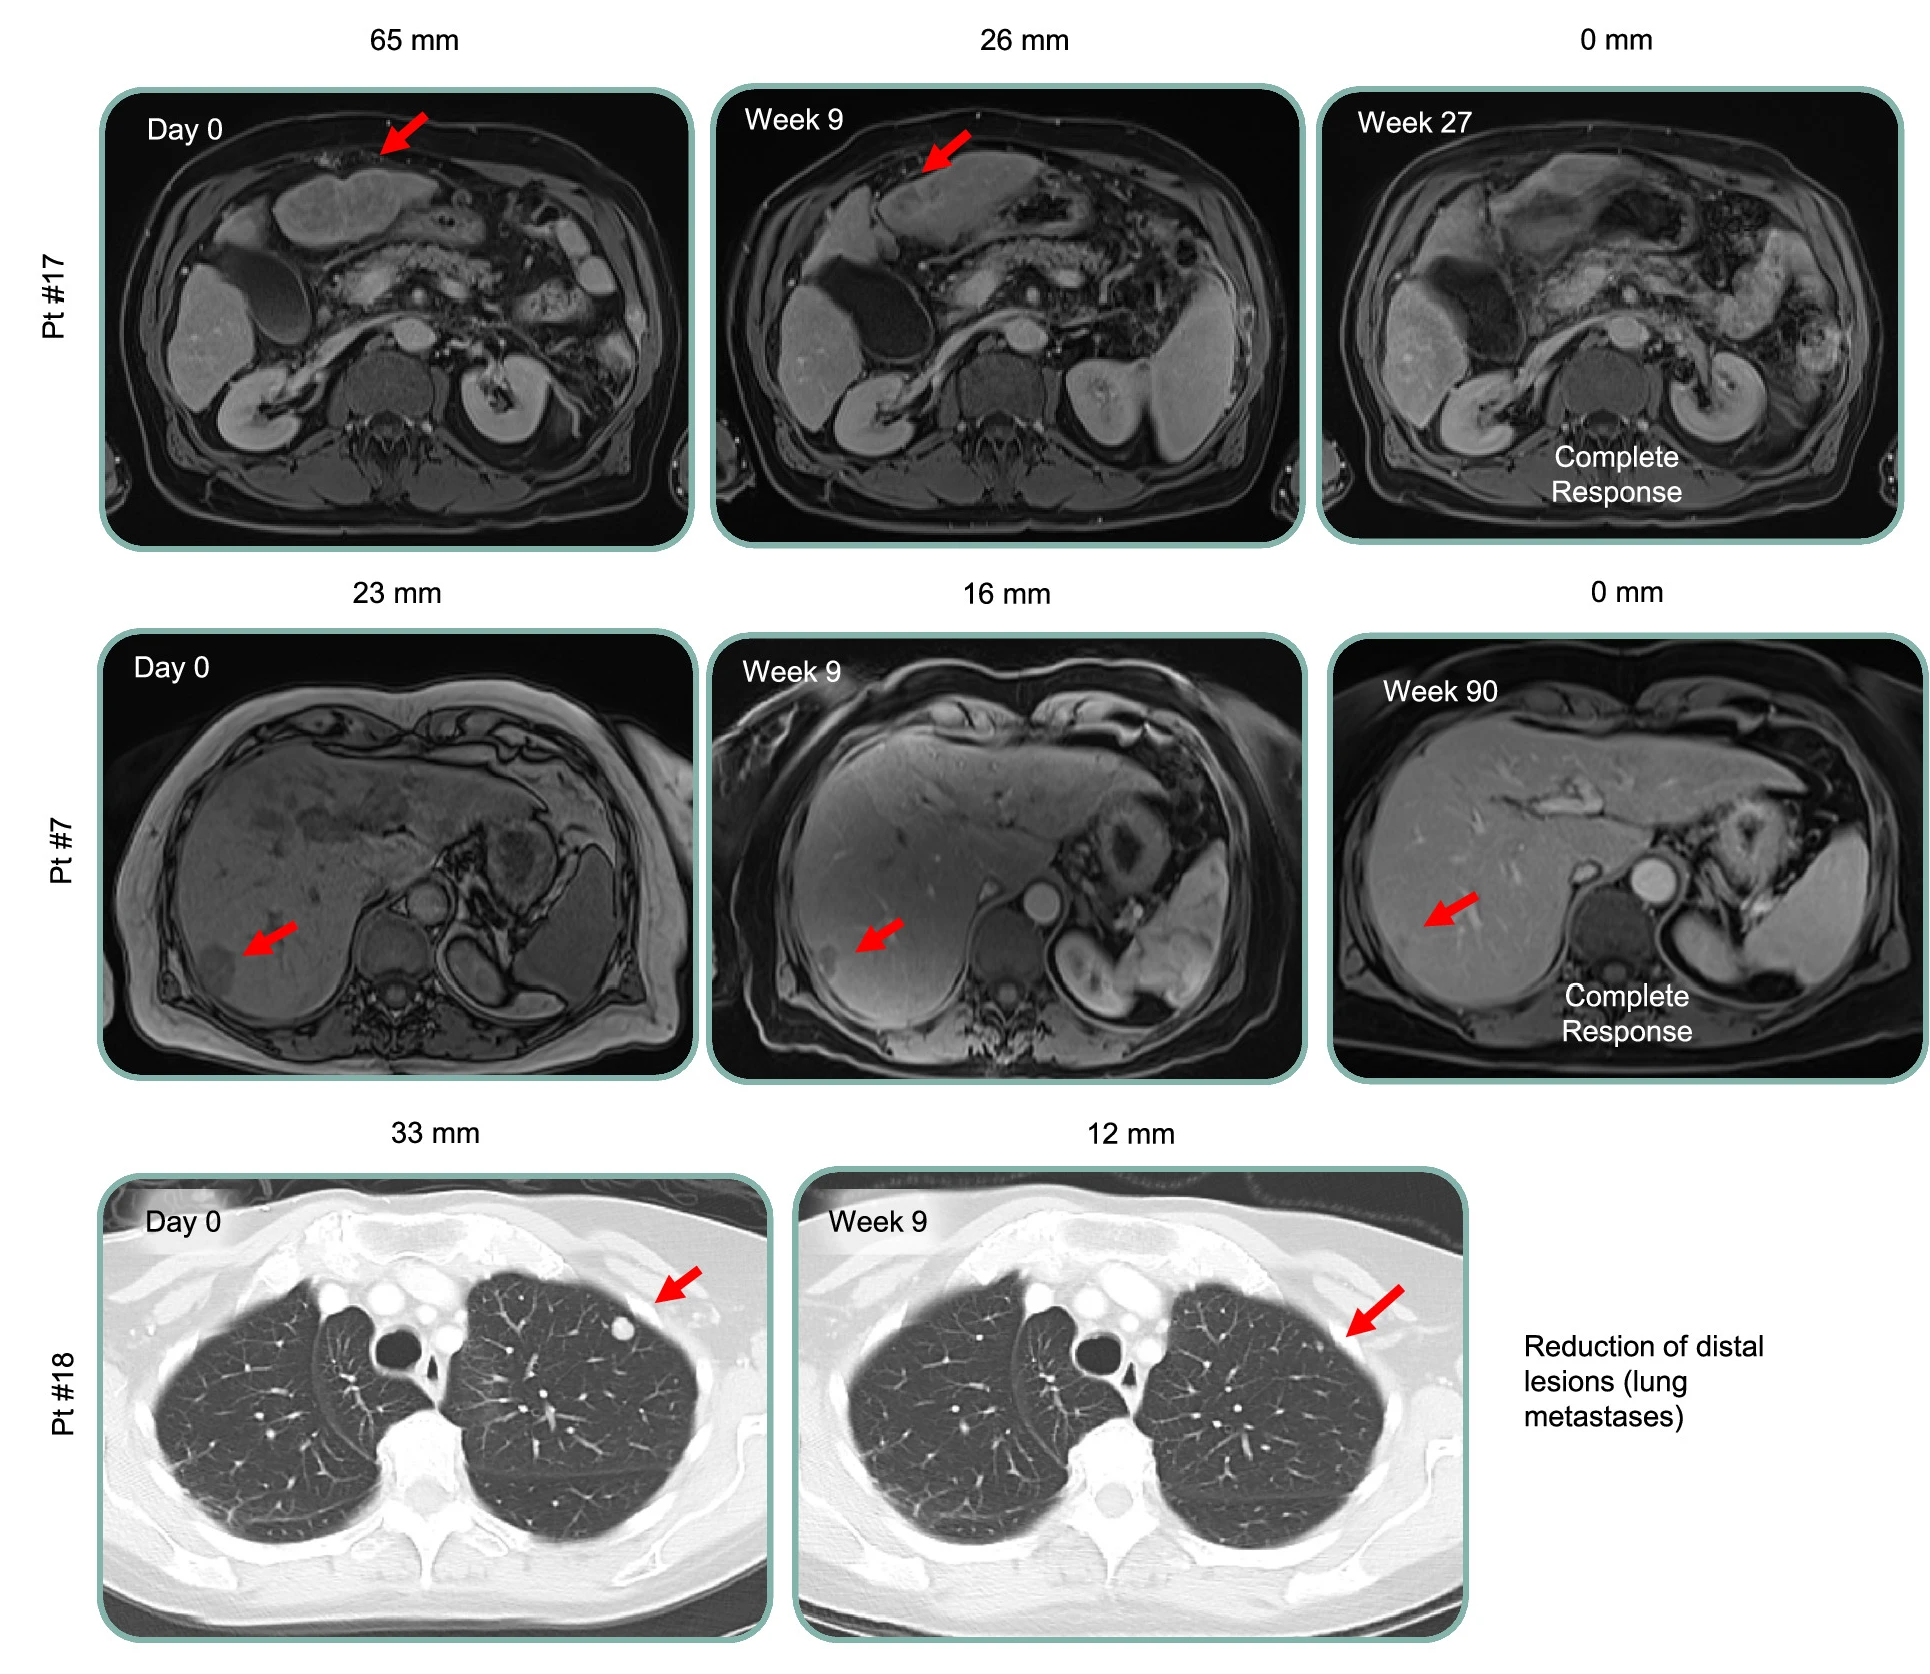

9月18日,Geneos Therapeutics宣布其研发的个性化癌症免疫疗法取得了重大突破,两名接受治疗的侵袭性癌症患者已分别持续治疗超过六年和五年,两位患者均实现完全缓解,未发生严重不良事件,目前均保持无复发健康状态。